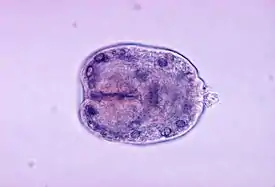

Возбудителем является личиночная стадия эхинококка Echinococcus granulosus. Половозрелая форма имеет длину 2—7 мм. Имеет головку с 4 присосками и двойную корону из 35—40 крючьев, шейку и 2—6 члеников. Личиночная стадия, растущая, развивающаяся и живущая в организме человека десятки лет, представлена кистой круглой или овальной формы, заполненной жидкостью. Окончательные хозяева — животные семейства псовых. Взрослые членики, выделяясь с калом, способны активно ползать, распространяясь по шерсти хозяина и в окружающей среде. Промежуточные хозяева — такие животные, как овцы, свиньи или коровы — заражаются, поедая траву, в которой могут оказаться яйца эхинококка. Окончательный хозяин заражается, поедая поражённые органы промежуточного.

Эхинококковые пузыри у животных и человека — тонкостенные образования округлой формы, заполненные светлой прозрачной жидкостью, содержащей дочерние и внучатые пузыри, формирующиеся из внутренней собственной оболочки пузыря, а отпочковываются снаружи его. Патогенное значение эхинококковых пузырей заключается в тяжёлой атрофии поражённых органов.[4]